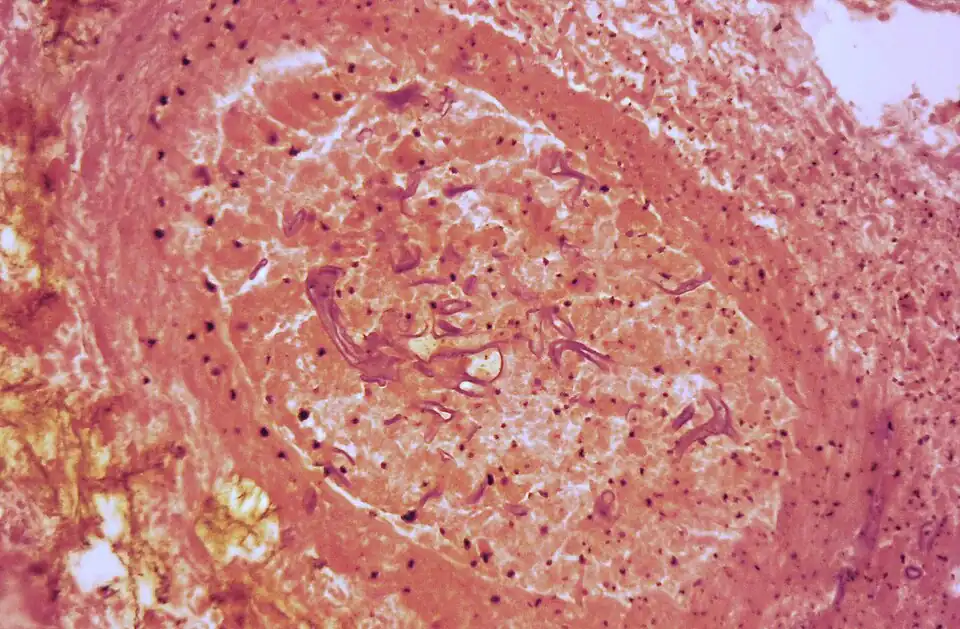

To confirm the diagnosis, biopsy samples can be cultured.[14][38] Culture from biopsy samples does not always give a result as the organism is very fragile.[18] Microscopy can usually determine the genus and sometimes the species but may require an expert mycologist.[18] The appearance of the fungus under the microscope can vary but generally shows wide (10–20 micron), ribbon-like filaments that generally do not have septa and that—unlike in aspergillosis—branch at right angles, resembling antlers of a moose, which may be seen to be invading blood vessels.[13][38]

-

Ribbon-like hyphae which branch at 90° -

Hyphae in blood vessel -